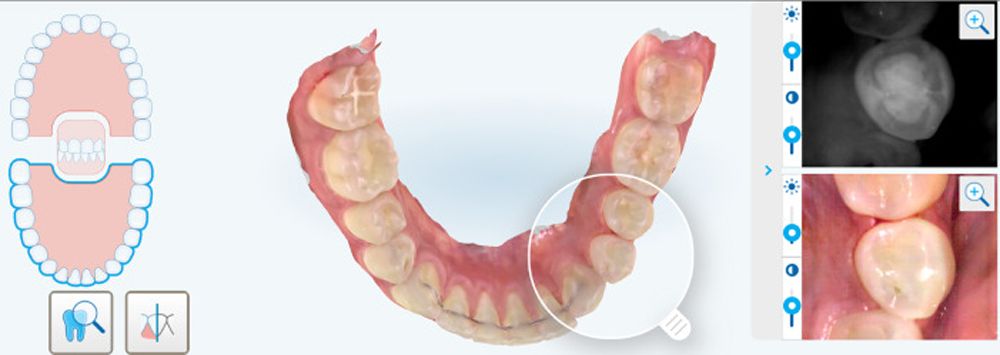

Align Technology announced findings of a study published in the peer-reviewed Journal of Dentistry titled “Reflected near-infrared light versus bite-wing radiography for the detection of proximal caries: a multicenter prospective clinical study conducted in private practices.” This study is said to demonstrate the value of the iTero Element 5D imaging system in caries detection and monitoring.

The study compared the detection of interproximal caries using near infrared technology (NIRI) and bitewing radiography. The study also compared NIRI and bitewing radiography to clinical removal of tooth decay. The iTero Element 5D’s imaging system and its NIRI was 66% more sensitive than bitewing x-ray technology and demonstrated 96% sensitivity for posterior interproximal lesions detections.

In the study, 100 patients in 5 dental clinics across Germany and Canada received intraoral scans using the iTero Element 5D imaging system. The imaging system scans the internal structure of the tooth in real time, which is designed to aid in caries detection. NIRI was found to be more sensitive than bitewing radiography in detecting early enamel lesions and comparable in detecting dentinal lesions.